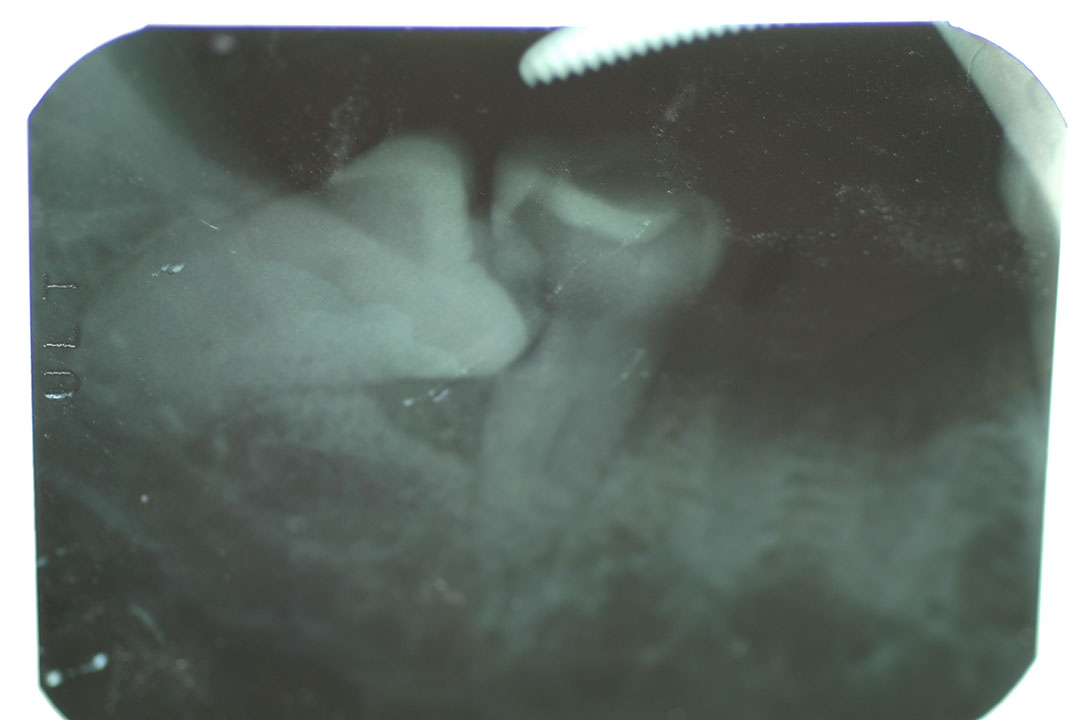

Implant 11a2.JPG

光牙醫